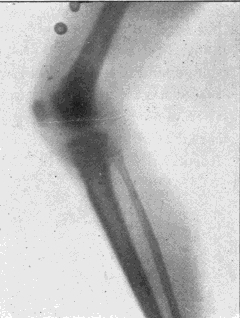

Fig. 4.—Knee, Knickerbocker Buttons, Bullet in Femur.